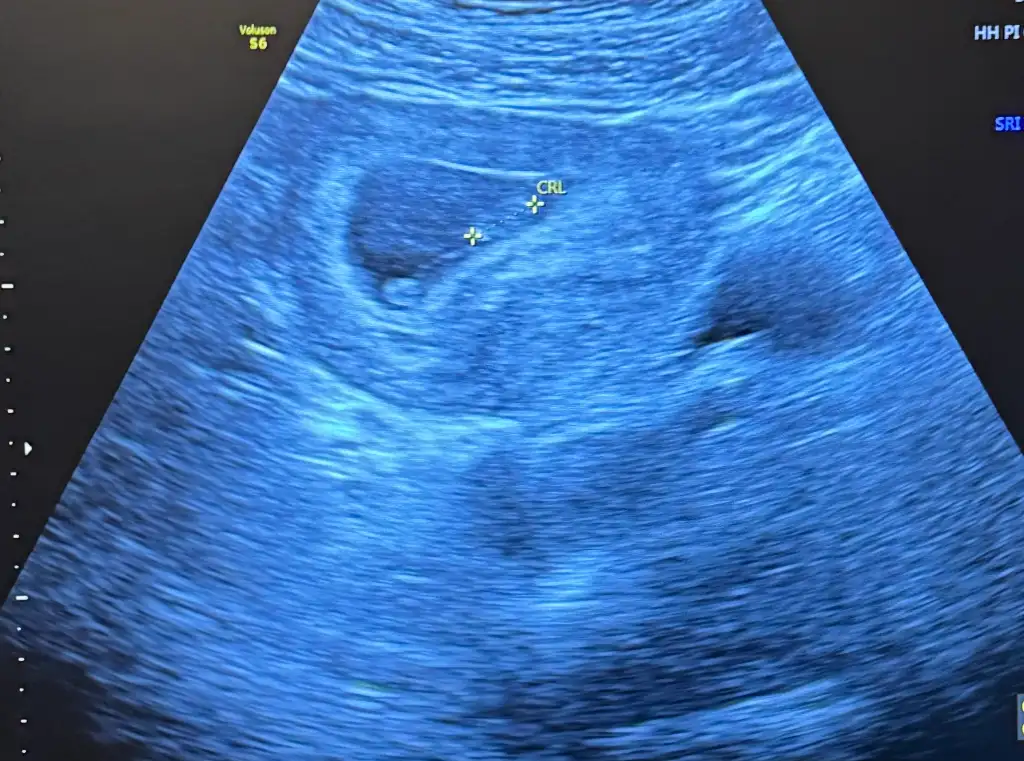

Banada bakarmısınız rica etsem 8 haftalık karından ultroson

Attığınız ultrasonda yolksac denen o kese hiç görünmüyor ama o yüzden plasenta da belli olmuyor yorum yapamayacağımbana da bakabilir misiniz? 6+3 haftalık abdominal

Ama yine de tahmin et derseniz erkek derimbana da bakabilir misiniz? 6+3 haftalık abdominal

Pazartesi hastaneye gideceğim fotoğraf alabilirsem onu da yüklerim belki o zaman daha iyi görünürAttığınız ultrasonda yolksac denen o kese hiç görünmüyor ama o yüzden plasenta da belli olmuyor yorum yapamayacağım

Bu yeni fotoğraf ama daha karışık sankiAttığınız ultrasonda yolksac denen o kese hiç görünmüyor ama o yüzden plasenta da belli olmuyor yorum yapamayacağım